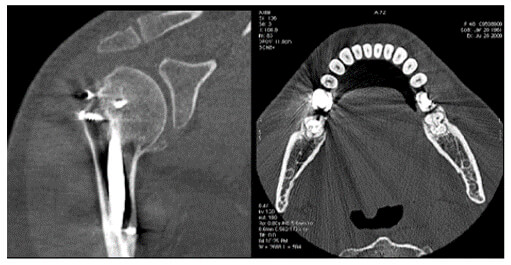

Metal implants such as shrapnel, surgical clips, pacers, joint prostheses, wires, pedicle screw placement, stenting, usually undergo follow-up CT imaging. These metallic implants lead to severe streak and shadow artifacts in CT images that superimpose the structures of interest and deteriorate image quality. This is because metallic objects are a high-density material, which is strongly scattered to the transmitted x-ray beam during CT examination.

Various metal artifact reduction techniques have been developed to reduce metal artifacts, and the most commonly used reconstruction algorithm for CT has filtered back projection (FBP), interpolation methods, and iterative reconstruction methods.

The formation of these artifacts is due to the impossibility of algorithms to take into consideration the very high-density values. This causes misinterpretation of images as the metals absorb more of the x-rays. This absorption creates shadows.

Compare the density of the prosthetic materials in these images all taken at 120 kV. As you can see, gold has the highest Hounsfield units.

As part of an operator’s role, patients should be asked to remove jewelry and dentures before starting the scans. This assists in avoiding some metallic related artifacts.

For non-removable items such as dental fillings and joint prosthesis, it is sometimes possible to use gantry angulation to exclude the metal inserts from scans of nearby anatomy.

It is also possible to adapt the kV values used based on the visualized structure or to use dual-energy protocols. Notice the difference in streaking in these three images.

Streaking caused by over ranging can be greatly reduced using special software corrections. Manufacturers use a variety of interpolation techniques designed to substitute the over ranged values in attenuations’ profile.

However, there is always a detail loss around the metal/tissue interface, which is often the area of interest in diagnosis.

This image shows the effectiveness of metal reduction artifact software. Notice how much better the resolution is in the image on the right.